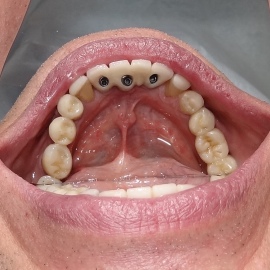

Pacjent z długą historią leczenia implantologicznego. Pierwsze implanty w pozycjach 23, 24 miał wkręcane w Warszawie przed 25 laty. Implant w pozycji górnego prawego kła ma agresywny gwint, ponieważ bezpośrednio po implantacji był obciążony (immediate loading) tymczasowym atachmentem ball abutmentv do stabilizacji tymczasowej protezy ruchomej. Kość szczęki regenerowana i odbudowywana etapami w całym górnym prawym kwadrancie. Pacjent planuje uzupełnić brakujące zęby 25, 26.